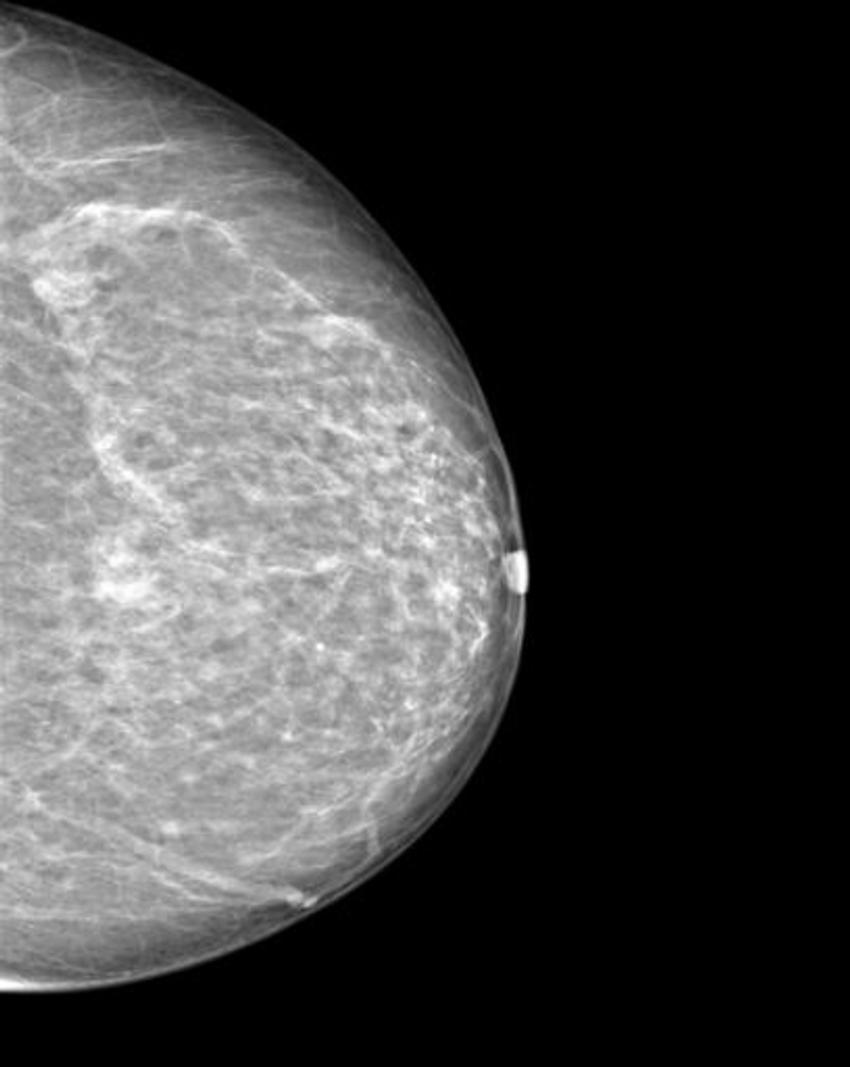

The researchers trained a cycle-consistent generative adversarial network (CycleGAN), a type of artificial intelligence application, on 680 mammographic images from 334 patients, to convert images showing cancer to healthy ones and to do the same, in reverse, for the normal control images. They wanted to determine if a CycleGAN could insert or remove cancer-specific features into mammograms in a realistic fashion.

The images were presented to three radiologists, who reviewed the images and indicated whether they thought the images were genuine or modified. None of the radiologists could reliably distinguish between the two.

"Neural networks, such as CycleGAN, are not only able to learn what breast cancer looks like," Dr. Becker said, "we have now shown that they can insert these learned characteristics into mammograms of healthy patients or remove cancerous lesions from the image and replace them with normal looking tissue."

Figure 4. Manipulated mammogram of breast in Figure 3 with a neural-network-generated mass.

High-res (TIF) version